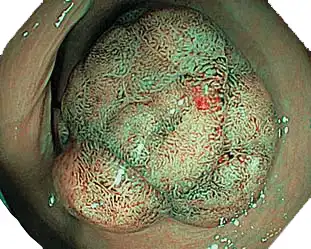

NBI(窄带成像)

NBI便于观察粘膜表面的毛细血管和其他结构。它有助于识别可疑区域。

近焦

通过近距离对焦,您可以将内窥镜的头端移动至离粘膜2mm附近,从而获得放大的特写图像。